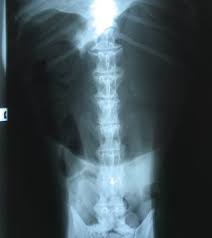

15 Best Pictures Cat X Ray Cost Philippines / Vet Services Does Paws Offer Vet Services Philippine Animal Welfare Society Paws Frequently Asked Questions Faqs. Common reasons for getting a cat x ray. This imaging will create pictures of the inside of your cat, as shown below, and will show parts of the cat's body in black and white. Find out what other people are paying, as well as what you should pay. He wasn't breathing right under anesthesia so the vet decided to stop the dental to wake him back up. Private institutions and clinics will of course cats need proper medical attention too, just like us.

How much do average veterinary x rays cost? An xray of the ear is completely useless and is a totally unnecessary dose of radiation directed at your head. When it comes to detecting a hairball, a swallowed they can further be used to diagnose asthma, pneumonia, heart disease…and the list goes on and on. Find out what other people are paying, as well as what you should pay. Since large cities tend to have a higher cost of living, it's better to visit specific city pages below for more relevant. They show a normal cat chest x ray. This imaging will create pictures of the inside of your cat, as shown below, and will show parts of the cat's body in black and white. Learn about cat x ray costs and important facts about them. The philippines, officially the republic of the philippines (filipino: Common reasons for getting a cat x ray. It is important to know what to expect and differences between. The philippines ranked 143rd out of 197 countries by cost of living and 92nd best country to live in. Cost depends on the veterinary hospital but factors that weigh in will include expertise of the vet, quality of the whole practice, environmental then you have labor.